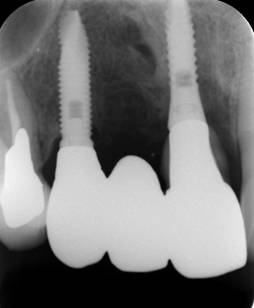

ストローマンインプラントとスプラインインプラント

術前

ストローマンインプラントとスプラインインプラントが隣り合わせに埋入されています.このころストローマンからスプラインに変えています。変えた理由は前歯部の審美性に優れていること、アバットメントの自由度があること、抜歯後すぐに埋入できるなどでした。

6年後。犬歯にコンポジット充填。第一大臼歯はメタルボンドになりました

8年後ほとんど変化がありません